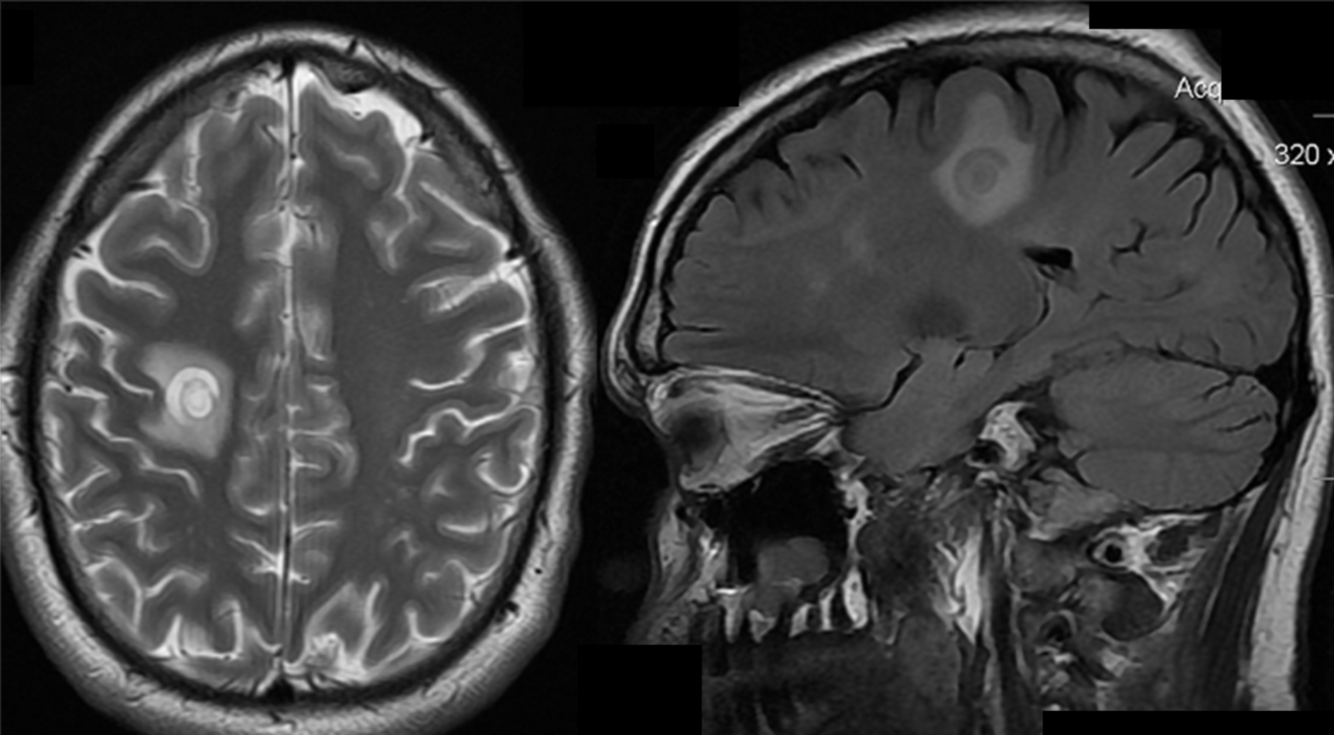

A 50 year-old man developed personality changes and subtle left-sided weakness.

Multiple sclersois - Tumefactive lesion